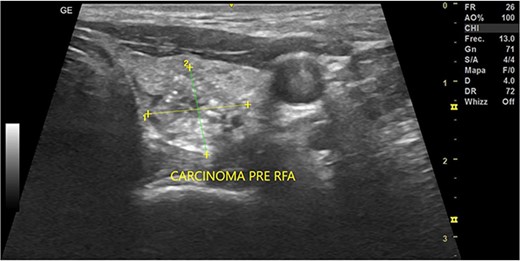

In May 2022, a thyroid ultrasound revealed a solid isoechoic left lobe TN measuring 12 × 11 × 13 mm, characterized by microcalcifications and irregular borders (Fig. 1). The color-flow Doppler ultrasound indicated increased perfusion, leading to its classification as a TI-RADS 5 nodule (Fig. 2). Elastography yielded a value of 2.2 (Fig. 3). Fine-needle aspiration confirmed Bethesda VI, consistent with thyroid papillary carcinoma.

Thyroid ultrasound: transversal view, left lobe nodule identification and measures. Pre-RFA procedure.